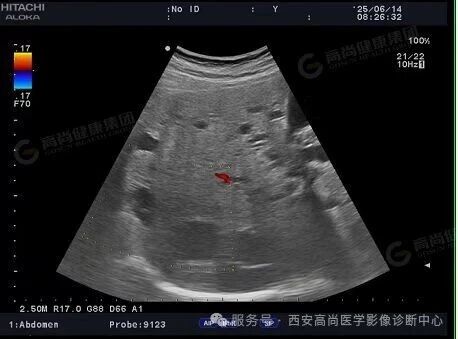

02超声图

03超声所见

肝脏声像图所见:考虑多囊肝;

双侧肾脏声像图所见:考虑多囊肾。

03、超声表现

肾脏: 双肾弥漫性增大,实质内布满大小不等的无回声区(囊肿),边界清晰,严重时正常肾实质被挤压消失。

肝脏: 肝内可见多个无回声区,分布不均,随病情进展囊肿数量和体积增加,肝脏增大。